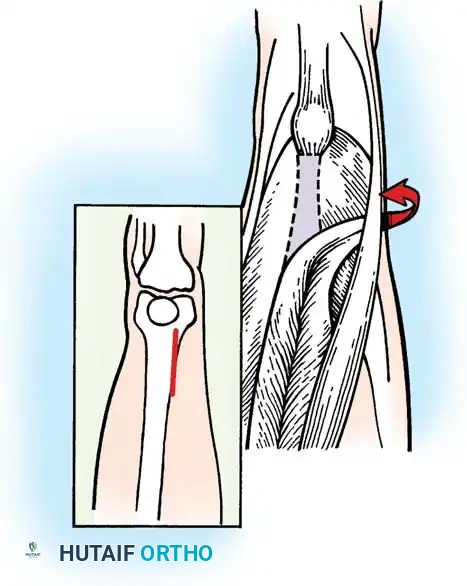

Fractional Lengthening of Hamstring Tendons (Technique 30-8)

Fractional lengthening allows for controlled elongation of the muscle-tendon unit while preserving the continuity of the muscle belly, thereby minimizing the risk of catastrophic over-lengthening and subsequent weakness.

Positioning and Approach:

* Place the patient in the prone position. Pad all bony prominences carefully.

* Exsanguinate the limb and inflate a proximal thigh tourniquet.

* Make medial and lateral posterior longitudinal incisions starting from the popliteal crease and extending 7 to 10 cm proximally. Alternatively, a single midline posterior incision can be utilized.

Incision mapping for posterior hamstring approach.

Medial Hamstring Lengthening:

* Divide the subcutaneous tissue and deep fascia strictly in line with the skin incision.

* Crucial Step: Identify and protect the posterior femoral cutaneous nerve in the proximal portion of the wound.

* Identify the hamstrings via blunt dissection. Isolate the semimembranosus muscle and incise its tendon sheath longitudinally.

* Divide the tendinous fibers of the semimembranosus on its deep (anterior) surface transversely at two distinct levels, leaving the underlying muscle fibers completely intact.

Forceps everting semimembranosus muscle to expose tendinous portion; division at two levels.

- Next, expose the semitendinosus tendon. Divide the distal portion of the tendon obliquely up to its muscle fibers. Depending on the severity of the contracture, incise the tendon transversely or perform a formal Z-plasty.

- Extend the knee and flex the hip simultaneously. The sectioned tendinous portion of the semimembranosus will slide smoothly over the intact muscle belly, achieving the desired lengthening.

Fig. 30-25 Fractional lengthening of hamstrings overview. A, Skin incision and incision in deep fascia over back of knee. B, Incisions in semimembranosus. C, Incisions in biceps femoris. D, Tendon sheaths of biceps femoris and semimembranosus are sutured before wound closure.